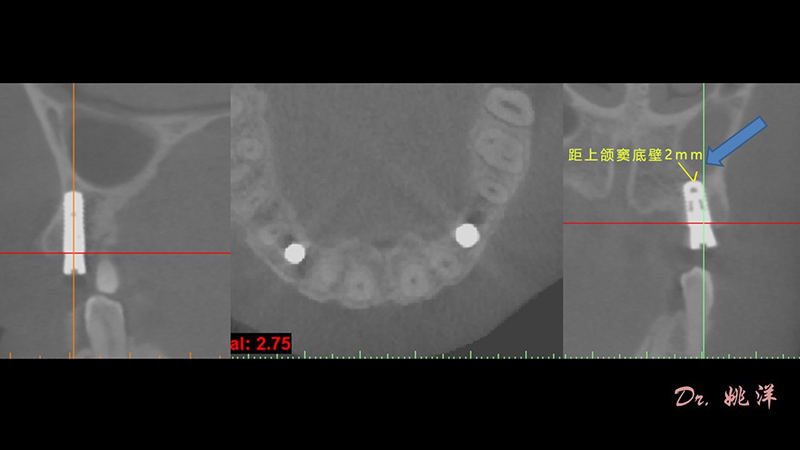

術(shù)前設(shè)計(jì)

冠狀面視圖

矢狀面視圖

軸狀面視圖

三維視圖

根據(jù)患者CT顯示,使用種植導(dǎo)航軟件設(shè)術(shù)前手術(shù)方案??紤]到患者拒絕手術(shù)摘除上頜竇囊腫等因素,此次手術(shù)選用了Straumann骨水平4.10*8.0mm的植體,植體末端位點(diǎn)設(shè)計(jì)距上頜竇底壁2mm處的同時(shí)兼顧種植方向和修復(fù)間隙,來(lái)達(dá)到理想的效果。